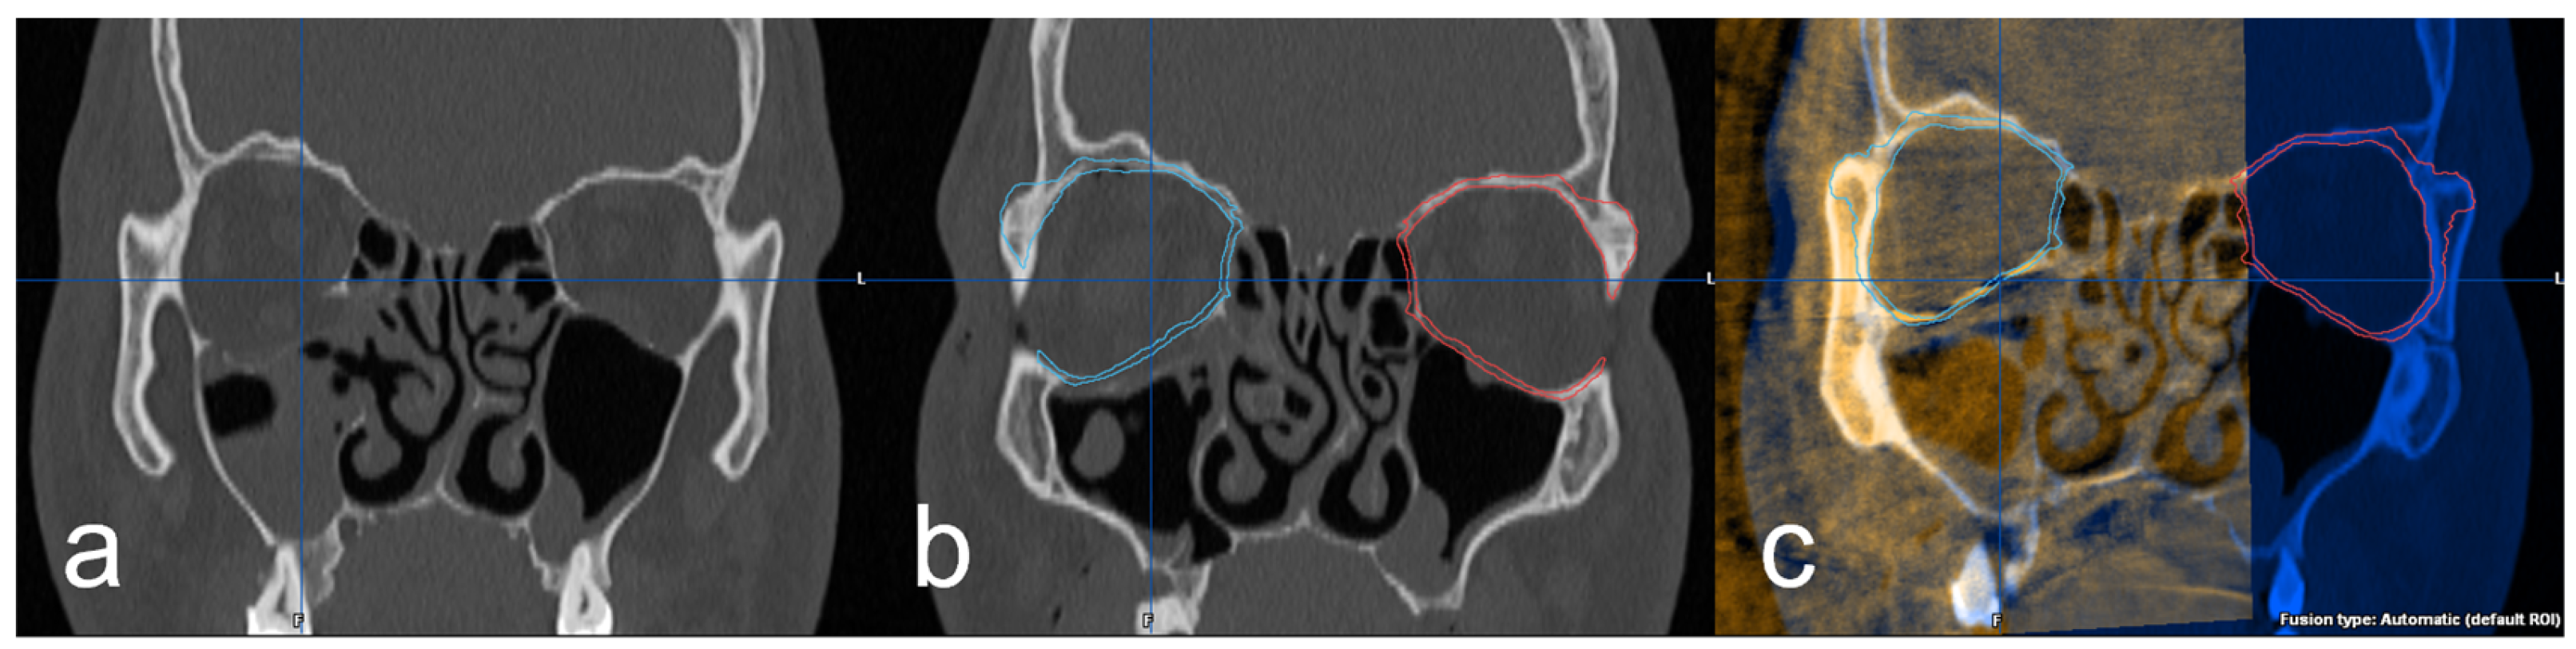

Further investigation of the 3D imaging was performed after importing the DICOM data into the software Brainlab© iPlan CMF™ 3.0 (Brainlab©, Munich, Germany). In the data set of the preoperative 3D imaging, the facial skull was segmented semi-automatically by the software. Subsequently, the intact orbit was mirrored onto the defect orbit in order to generate the structures of an anatomically correct orbit and also in the areas of the bony defect (Figure 3a,b). Using the “smartbrush function” of the software, the parts of the digitally reconstructed orbit that deviated from the existing bone structure were now touched up. Afterward, the digital orbita, which had been ideally reconstructed for each case, was checked for accuracy by a specialist in maxillofacial surgery together with the examiner according to the four-eyes principle. A classification was also made according to the complexity of the fracture: (1) simple orbital floor fracture, (2) severe orbital floor fracture with clear extension to the dorsal, (3) orbital floor fracture with involvement of the medial orbit and (4) severe orbital floor fracture with complex extension to medial and dorsal. In the next step, the intraoperative/postoperative imaging of the corresponding case was imported into the iPlan CMF™ 3.0 software. This was followed by the fusion and superimposition with the preoperative data set, including the idealized reconstructed orbit (Figure 3c). The software’s “autofusion function” was used for this and, if necessary, optimized manually again.

Figure 3.

(a) coronal view of the right orbital floor fracture, (b) representation of the segmented intact left orbita (red) and mirroring to the right defect side (blue) and (c) fused intraoperative imaging with superimposition of the implant and the digitally reconstructed orbita (blue).